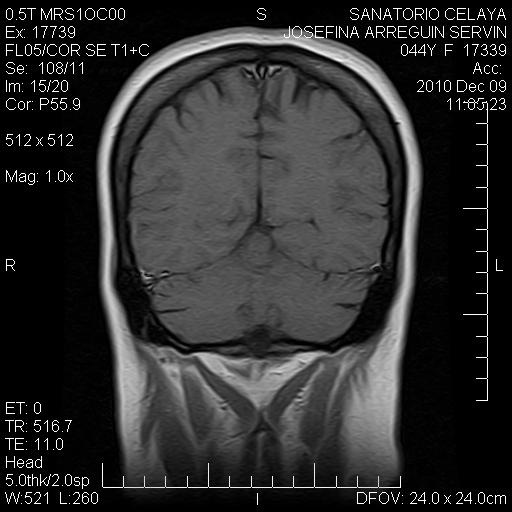

En esta imagen me llama la atención el engrosamiento uniforme de las circunvoluciones del lóbulo temporal, especificamente de la corteza cerebral, si se comparan con el lóbulo temporal izquierdo hay una diferencia notoria, por otra parte, también hay hiperintensidad en la circunvolución adyancente a la insula derecha. La substancia blanca en estas zonas se ve isointensa.